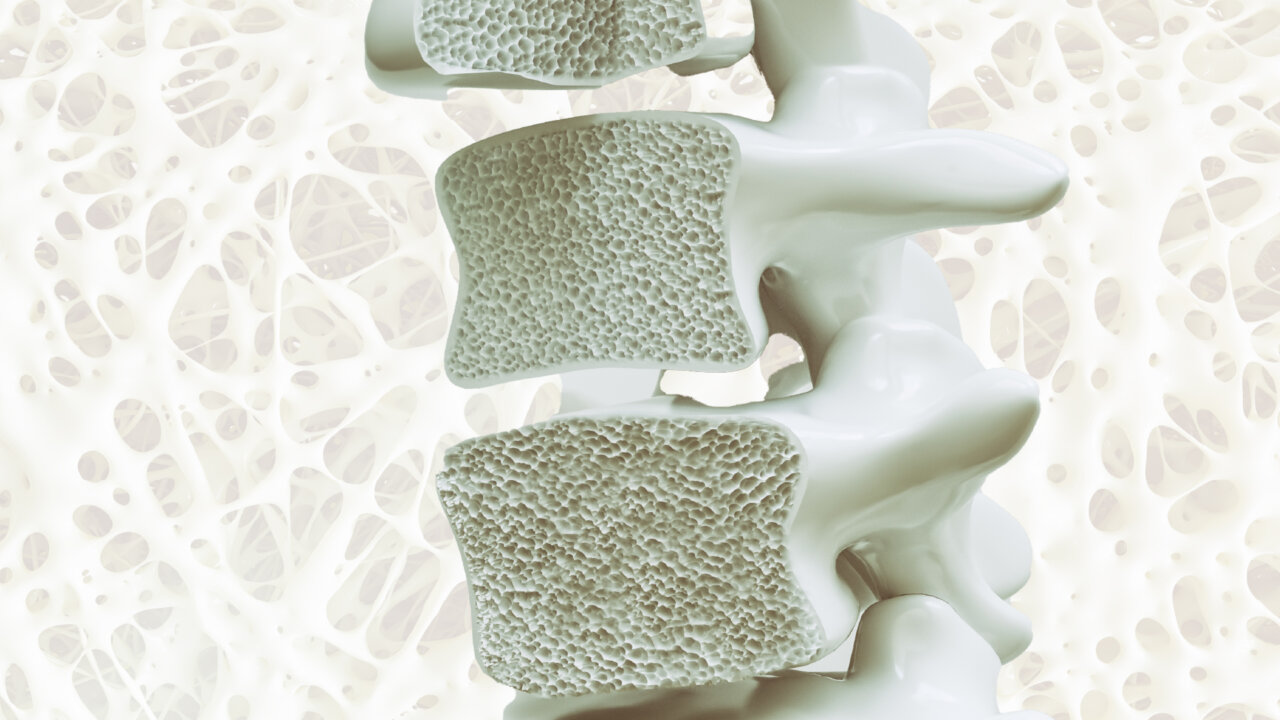

ผู้ชายมีความเสี่ยงเรื่องภาวะกระดูกพรุน แม้ผู้ชายจะมีฮอร์โมน แอนโดรเจน (Androgen) ซึ่งช่วยสร้างมวลกระดูกได้มากในช่วงวัยกลางคน จึงทำให้เข้าสู่ภาวะกระดูกพรุนช้ากว่าผู้หญิงเฉลี่ย 10 ปี แต่สุดท้ายเมื่ออายุมากขึ้น เซลล์ที่ควบคุมสมดุลกระดูกเริ่มทำงานผิดปกติ โดยเฉพาะการทำงานของเซลล์ที่เกี่ยวกับกระดูก เนื่องจากร่างกายมีเซลล์ 2 ชนิดที่ทำหน้าที่ตรงข้ามกัน คือ เซลล์สร้างกระดูก (Osteoblast) และเซลล์สลายกระดูก (Osteoclast) เมื่ออายุมากขึ้น การสร้างกระดูกจะลดลง ขณะที่การสลายยังคงดำเนินต่อไป นำไปสู่ภาวะที่มวลกระดูกค่อย ๆ ลดลงเรื่อย ๆ จนเสี่ยงต่อการหักหรือยุบตัวของกระดูกโดยเฉพาะ “กระดูกสันหลัง”

“กระดูกสันหลังเป็นจุดรับน้ำหนักของร่างกาย เมื่อมวลกระดูกลดลง ความแข็งแรงก็ลดตาม ส่งผลให้กระดูกสันหลัง ยุบตัว หรือผิดรูป ได้ง่าย ทำให้เกิดอาการปวดหลังเรื้อรัง หรือแม้แต่เดินไม่ได้ในรายที่กระดูกหักและไปกดทับเส้นประสาท” นพ.ศรัณย์กล่าวเพิ่มเติม

“กระดูกสันหลังเป็นจุดรับน้ำหนักของร่างกาย เมื่อมวลกระดูกลดลง ความแข็งแรงก็ลดตาม ส่งผลให้กระดูกสันหลัง ยุบตัว หรือผิดรูป ได้ง่าย ทำให้เกิดอาการปวดหลังเรื้อรัง หรือแม้แต่เดินไม่ได้ในรายที่กระดูกหักและไปกดทับเส้นประสาท” นพ.ศรัณย์กล่าวเพิ่มเติม